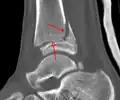

A triplane fracture of the ankle as seen on plain X-ray

A triplane fracture of the ankle as seen on CT

- Triplane fractures are a special type of fracture that involves the immature skeleton. It has a coronal plane in the metaphysis, an axial plane in the physis, and a sagittal plane in the epiphysis.[14]